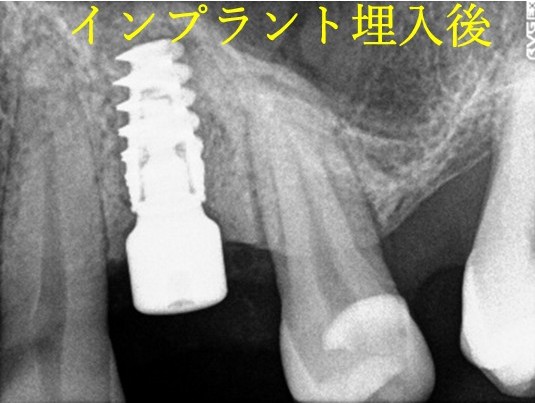

Before

インプラント埋入前

義歯を装着したところ

使用していた部分入れ歯

After

インプラント埋入後